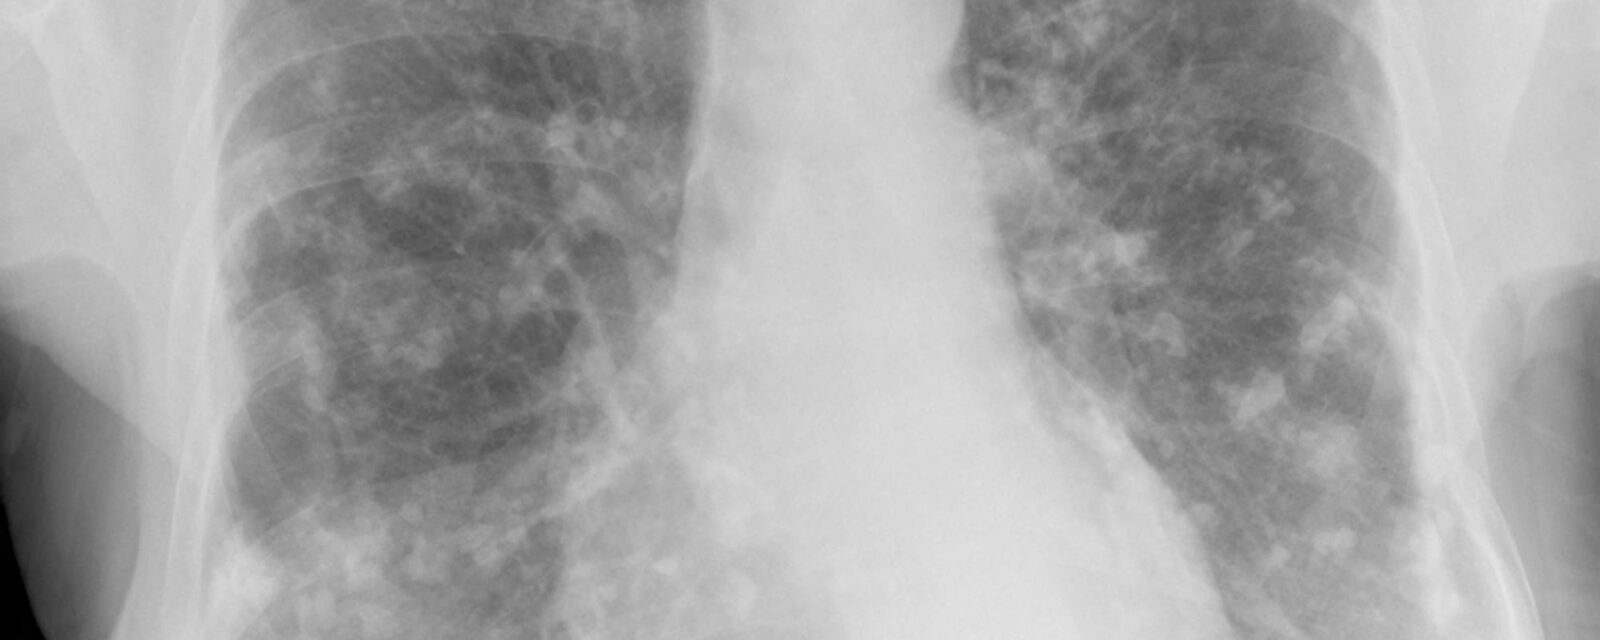

Since symptoms do not occur, a person is often diagnosed when undergoing radiography or CT imaging scans for other issues. The plaques typically occur in the parietal area of the pleura, which is the outer layer that lines the inner surfaces of the thoracic cavity. Plaques most often form in the lower portions of the chest.

X-ray imaging scans reveal grey-white areas of pleural thickening in the shape of a holly leaf. Most incidences of the plaques are found through x-ray scans. Calcified plaques can be difficult to identify through X-ray as they appear translucent or white in the lungs. A computerized tomography (CT) scan uses computer processing combined with X-ray images of different body angles to create cross-sectional images, or slices, of the bones, blood vessels, and soft tissues. Since calcified plaques can appear translucent, a CT scan can provide a more detailed image compared to an X-ray. Even if the plaques are not calcified, CT scans are the best way to diagnose this condition.